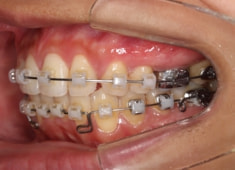

治療開始時